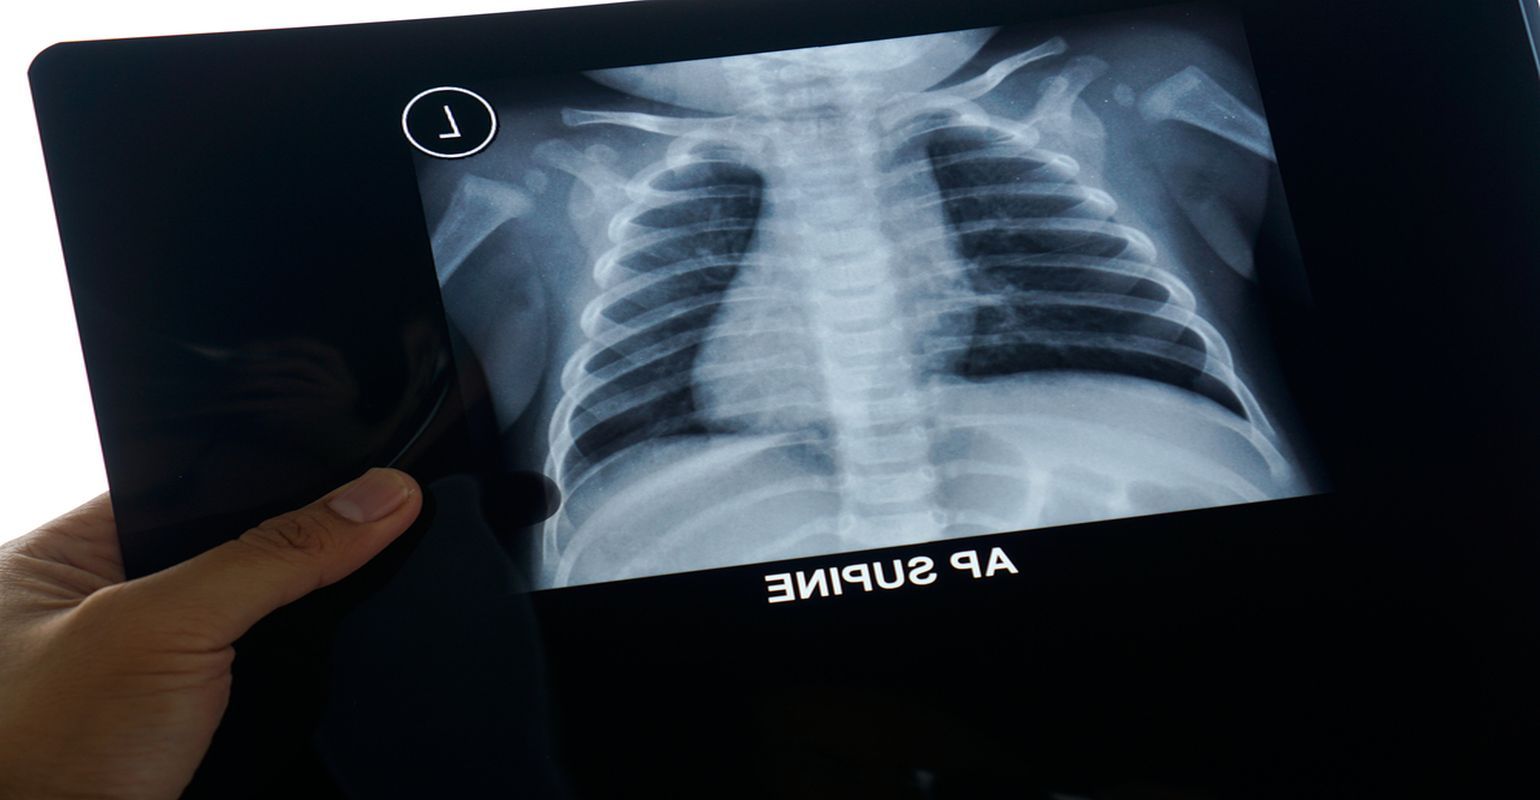

Baby chest x ray pneumonia Thursday March 24 2022 Respiratory syncytial virus or RSV most commonly seen in children under age 5 Parainfluenza virus. Pneumonia is not always seen on x-rays either because the disease is only in its initial stages or because it involves a part of the lung not easily seen by x-ray. An important test for making a diagnosis of pneumonia is a chest x-ray.

7 if a child. There is a problem with. Video will describe how pneumonia may look like on a chest x-ray.

The study included 167 children aged more than 12 months. Although the chest x. A chest X-ray is often used to diagnose pneumonia.